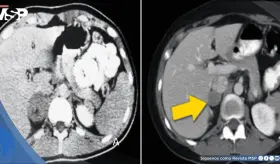

La paciente presentaba múltiples factores de riesgo incluyendo uso de ...

Las imágenes sugerían infiltración linfomatosa, pero la esplenectomía ...

Paciente presenta ruptura intraperitoneal de quiste parasitario después de presión abdominal súbita, manifestando dolor intenso en hipocondrio derecho con irradiación al hombro.